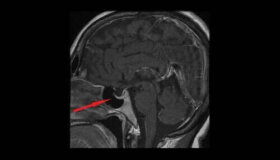

뇌하수체 선종은 성장 속도가 느린 양성 종양이다. 신체의 다른 땀샘의 기능을 조절하는 뇌하수체를 구성하는 세포에 생긴다. 뇌하수체 선종은 비교적 흔한…